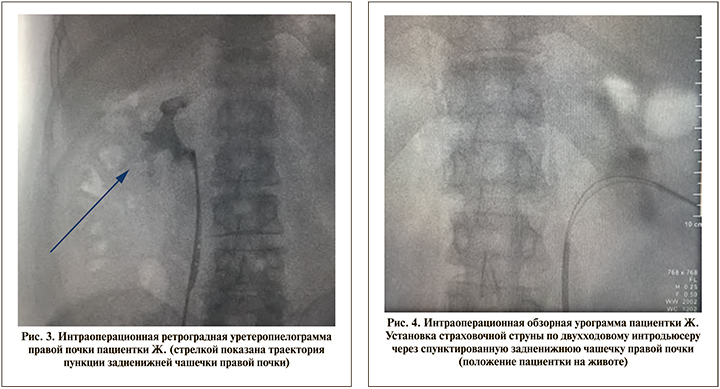

15.06.2021 пациентке выполнено оперативное лечение в объеме миниперкутанной нефролитотрипсии справа. Оперативное вмешательство проходило без особенностей. Первым этапом установлен мочеточниковый катетер с наружным выведением диаметром 7 French (Fr), по которому выполнена ретроградная уретеропиелография (рис. 3).

В положении пациентки на животе выполнена пункция правой почки через задненижнюю чашечку в проекции аваскулярной зоны Броделя. По окончании пункции установлены (по канюле иглы) основная гидрофильная и (по двухходовому интродьюсеру) страховочная гидрофобная струны-проводники (рис. 4).